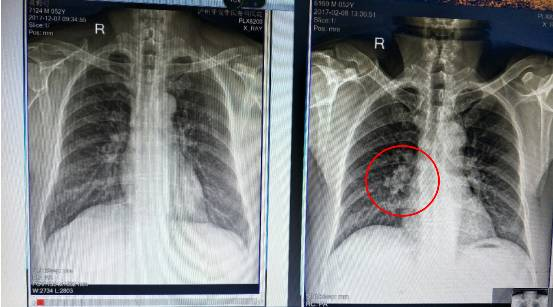

在2003年的矽肺疫情中,陈长安针对21名重症矽肺患者展开治疗。50天临床观察显示:95.2%患者症状消失、30.8%肺功能完全恢复、33.3%胸片病灶吸收——三项指标刷新当时尘肺病治疗纪录。这一成果不仅让患者看到了生的希望,也为尘肺病的治疗带来了新的曙光。